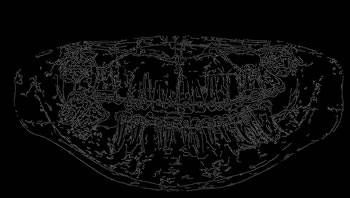

Refer to caption

Figure 7: Steps of the performance analysis of segmentation algorithms.

Only the image ROIs were considered to calculate the metrics for the evaluation of the segmentation methods. The process presented in Figure 6 was carried out on all the segmented images obtained by each one of the 10 segmentation methods analyzed. Figure 7 illustrates the steps of the performance evaluation over 10 segmentation methods (see also Table 9 for a list of the evaluated methods).